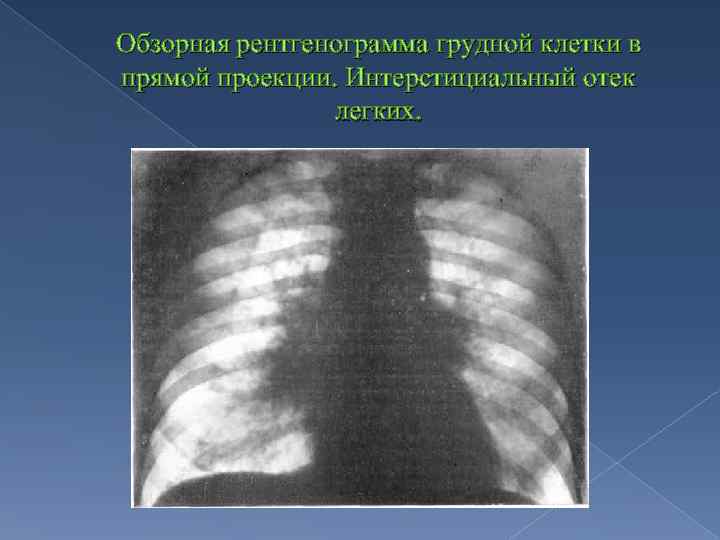

Ячеистая деформация легочного рисунка: медицинская визуализация